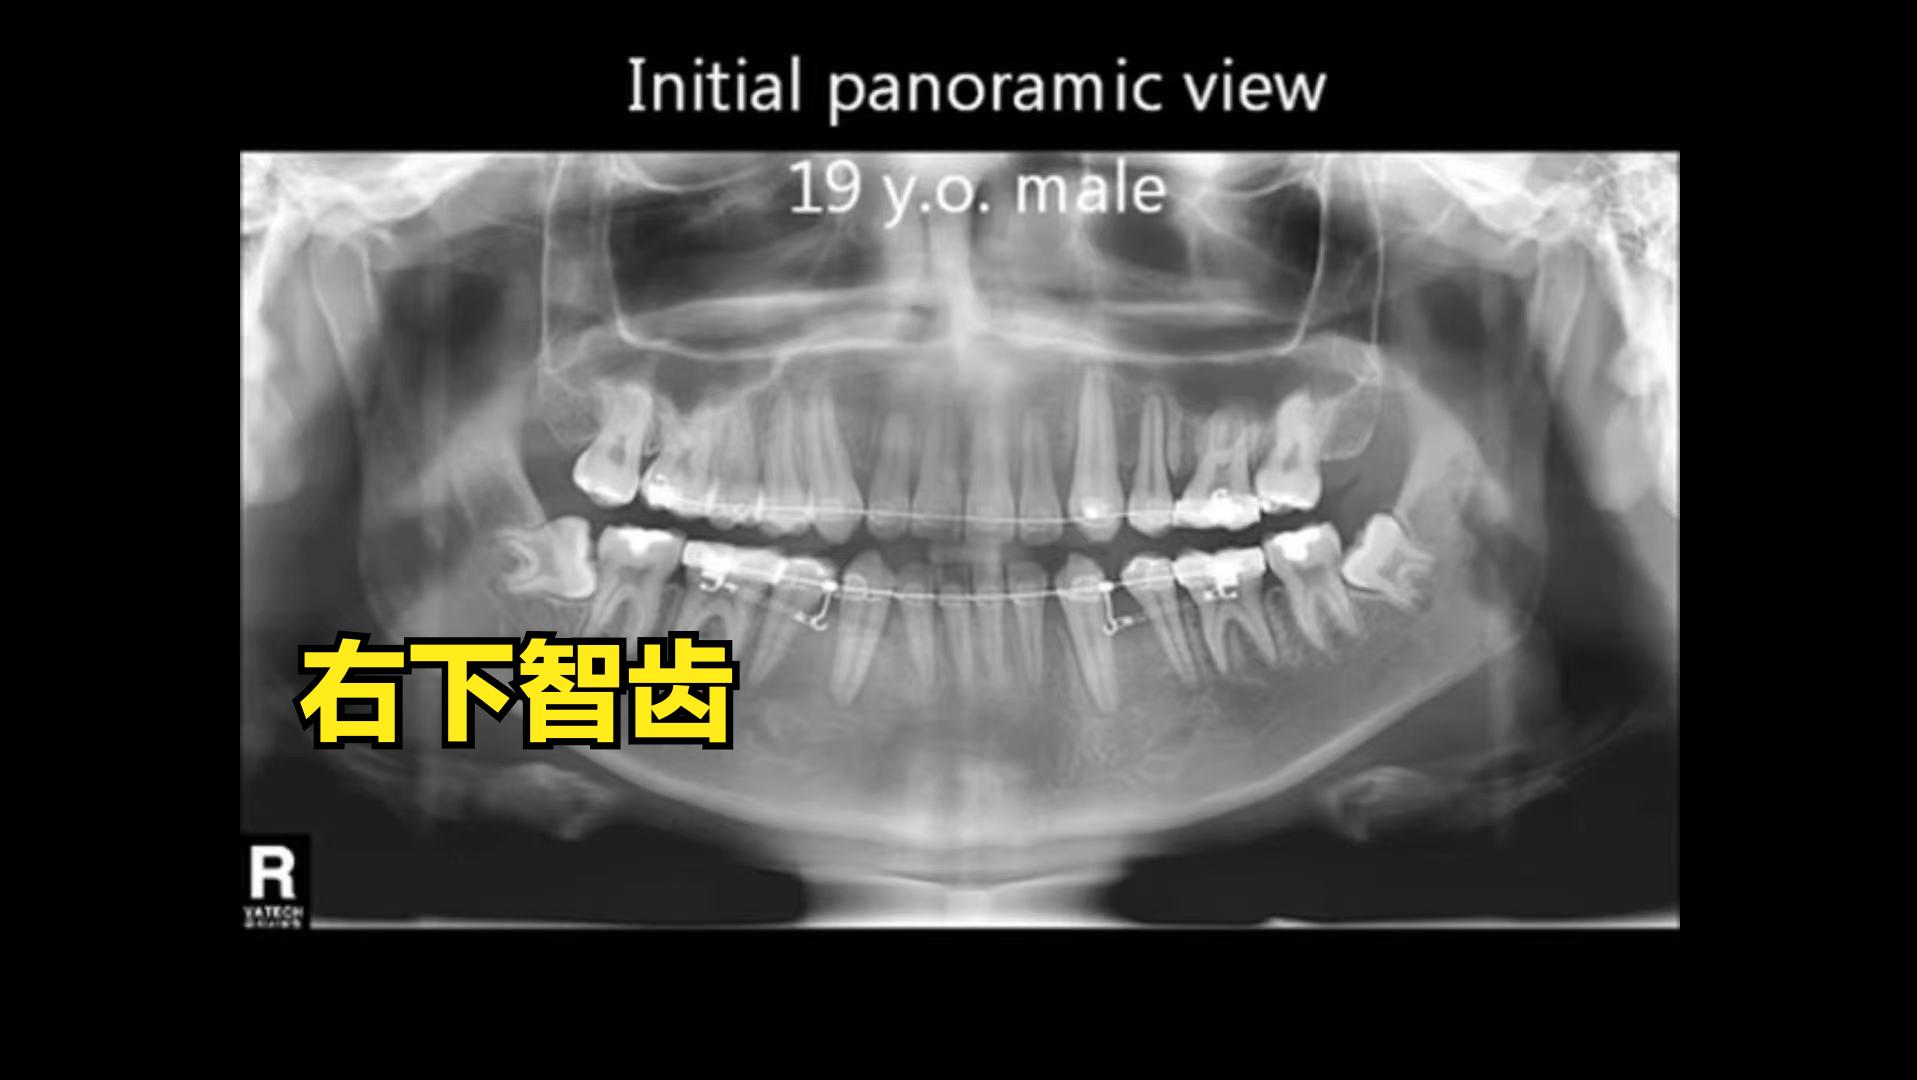

(1)术前评估:x线片:患者要求拔除右下智齿,右下智齿水平阻生,根尖近神经管。